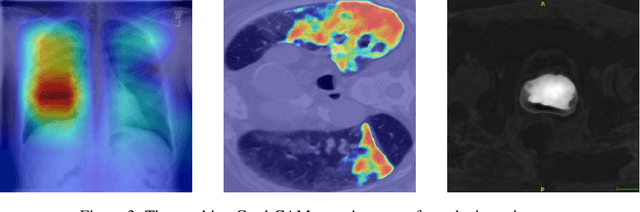

Abstract:Automatic segmentation of ground glass opacities and consolidations in chest computer tomography (CT) scans can potentially ease the burden of radiologists during times of high resource utilisation. However, deep learning models are not trusted in the clinical routine due to failing silently on out-of-distribution (OOD) data. We propose a lightweight OOD detection method that leverages the Mahalanobis distance in the feature space and seamlessly integrates into state-of-the-art segmentation pipelines. The simple approach can even augment pre-trained models with clinically relevant uncertainty quantification. We validate our method across four chest CT distribution shifts and two magnetic resonance imaging applications, namely segmentation of the hippocampus and the prostate. Our results show that the proposed method effectively detects far- and near-OOD samples across all explored scenarios.

Abstract:Automatic segmentation of lung lesions in computer tomography has the potential to ease the burden of clinicians during the Covid-19 pandemic. Yet predictive deep learning models are not trusted in the clinical routine due to failing silently in out-of-distribution (OOD) data. We propose a lightweight OOD detection method that exploits the Mahalanobis distance in the feature space. The proposed approach can be seamlessly integrated into state-of-the-art segmentation pipelines without requiring changes in model architecture or training procedure, and can therefore be used to assess the suitability of pre-trained models to new data. We validate our method with a patch-based nnU-Net architecture trained with a multi-institutional dataset and find that it effectively detects samples that the model segments incorrectly.

Abstract:M3d-CAM is an easy to use library for generating attention maps of CNN-based PyTorch models improving the interpretability of model predictions for humans. The attention maps can be generated with multiple methods like Guided Backpropagation, Grad-CAM, Guided Grad-CAM and Grad-CAM++. These attention maps visualize the regions in the input data that influenced the model prediction the most at a certain layer. Furthermore, M3d-CAM supports 2D and 3D data for the task of classification as well as for segmentation. A key feature is also that in most cases only a single line of code is required for generating attention maps for a model making M3d-CAM basically plug and play.